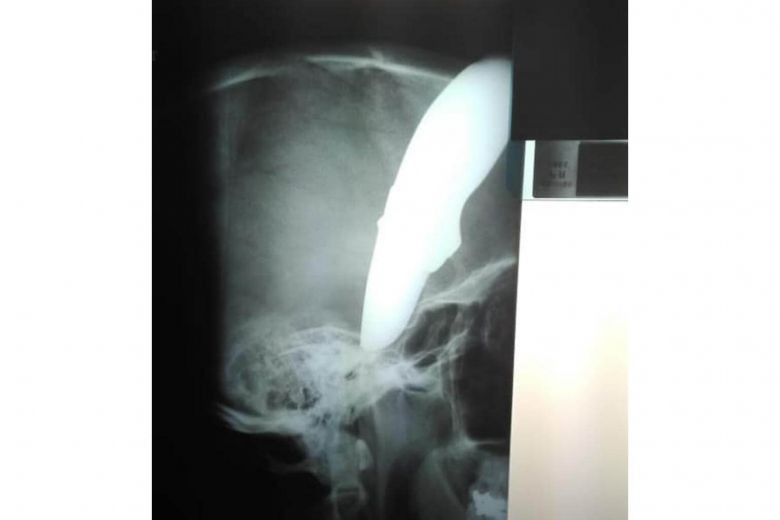

Ảnh chụp X-quang. Ảnh: Facebook

Theo người phát ngôn bệnh viện Tygerberg, bệnh nhân hiện trong tình trạng ổn định. "Ông Wayne đã rất may mắn vì con dao đâm vào hộp sọ nhưng bị cong do chạm trúng xương. Lưỡi dao chệch xuống mặt bệnh nhân bên ngoài hộp sọ" – bác sĩ Venter cho biết thêm.

Cựu vận động viên xe đạp Wimpie van der Merwe, 61 tuổi, đã đăng tải hai bức ảnh ông Wayne với con dao cắm xuyên đầu và ảnh chụp X-quang lên Facebook. Cựu vận động viên này cho biết mình cũng bị tấn công ở cùng địa điểm cách đó 1 tuần.